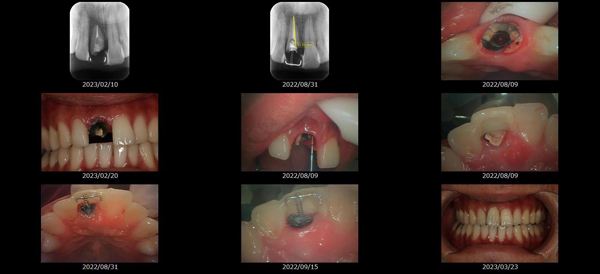

救歯MTM

虫歯が大きくて残せない歯、転倒などの事故により歯が根の深いとこで折れてしまったなどで、抜かざるを得ない歯を、骨の中に埋まっている健全な根を、骨の上に矯正的に引き上げることで、その歯を抜かず温存、救歯できる可能性のある治療方法です。

この特別な診療である救歯MTMは、以下のような特徴があります。

①健全な歯を、歯肉から見える位置にまで引き上げることで

根の治療の成功率を上げることが出来る。唾液には沢山の細菌がいます。唾液が入らない環境での根の治療を(神経の治療)を行うことで神経の治療、根の治療の成功率は格段と上がります。

②骨の上にある歯と土台で支える被せもの製作できる。

被せものを土台だけに頼ることなく、引き上げた健全な歯でも支えることで、歯への被せ物がしっかりと装着できるようになる。

③抜かずに歯を活かすことで、隣の歯を削るブリッジやインプラントにしないで済むことがある。

歯を矯正的に引き上げることで、その歯を救歯できるだけでなく、隣の歯を削るなどの侵襲を回避できる場合がある。

リスク

- > 歯を矯正的に引き上げることで、骨の中の根の長さは短くなりますが、その短さでも安定するという診断をした場合のみ施術になります。 残せる歯、根の長さが短い場合は、この救歯MTMの治療対象とならない場合がございます。

- > 治療期間が数か月~1年に及ぶ場合がある。

- > 費用が自費診療 44,000円 ~ 66,000円

- > 救歯MTMは救歯BTAセラミックと併用治療が必要な場合があります。

症例